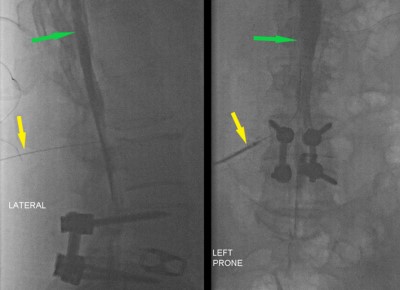

Myelogram - Fluoroscopic images of lumbar spine in the lateral (left) and AP (right) planes. Both images show results of recent lumbar spine surgery. Seen in both images is a needle that has been placed into spinal canal (lumbar puncture, yellow arrow). X-ray dye has been injected into the spinal canal and ascending up the back (green arrow). Note the dye outlining the lumbar nerve roots of the cauda equina.